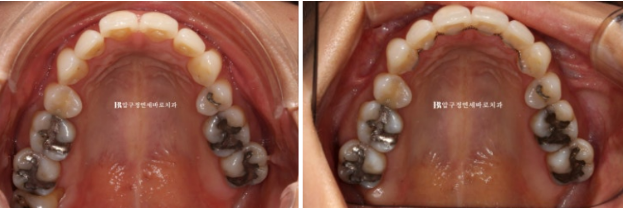

23.04~23.08

철사 유지장치까지 이물감 없이 깔끔하게 들어간 모습입니다.